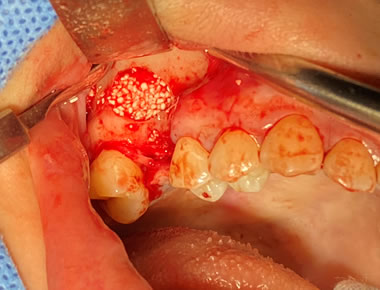

上顎外側骨隆起 症例2(上顎の頬側にできた骨隆起)

笑った時にゴボ口となりやすく、隆起した部分に食物残渣などが生じやすいケースです。静脈麻酔で約1時間半程度要します。

料金

静脈内鎮静法による麻酔代込:約20万円(保険適用外)